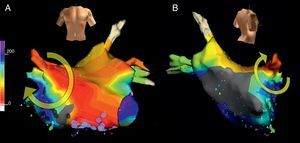

Taquicardia macrorreentrante auricular izquierdaLa estructura anatómica de la AI no contiene los grandes obstáculos de la AD, y quizá por eso las TAMR de la AI han sido poco frecuentes. En pacientes sin antecedentes de cirugía la TAMR de AI se produce en presencia de amplias áreas inexcitables de bajo voltaje y áreas de bloqueo de conducción que forman el núcleo central del circuito, ya sea por sí mismas, ya sea por su anexión a algún obstáculo anatómico (orificios de las venas pulmonares u orejuela) (Figura 12, Figura 13)17, 26, 27. La TAMR de AI se asocia a cardiopatías orgánicas (miocardiopatías, valvulopatías) y a patrones de grave trastorno de conducción interauricular (bloqueo del haz de Bachmann)28. Un sustrato frecuente de la TAMR de AI son las atriotomías quirúrgicas de cirugía valvular mitral29 o de cirugía de fibrilación auricular30. En los últimos años, el gran auge de la ablación de la fibrilación auricular, con destrucción de amplias zonas de miocardio auricular, ha dado pie a una alta incidencia de TAMR de la AI en estos pacientes31, 32, 33, que lleva a la necesidad de nuevos procedimientos de ablación en un buen número de ellos.

Figura 13. Cartografía electroanatómica (Navx®) en visión anterior (A) y posterolateral derecha (B) de una taquicardia auricular macrorreentrante girando en torno a la vena pulmonar superior derecha. Obsévense las zonas inexcitables de bajo voltaje, especialmente en la aurícula izquierda posterior.